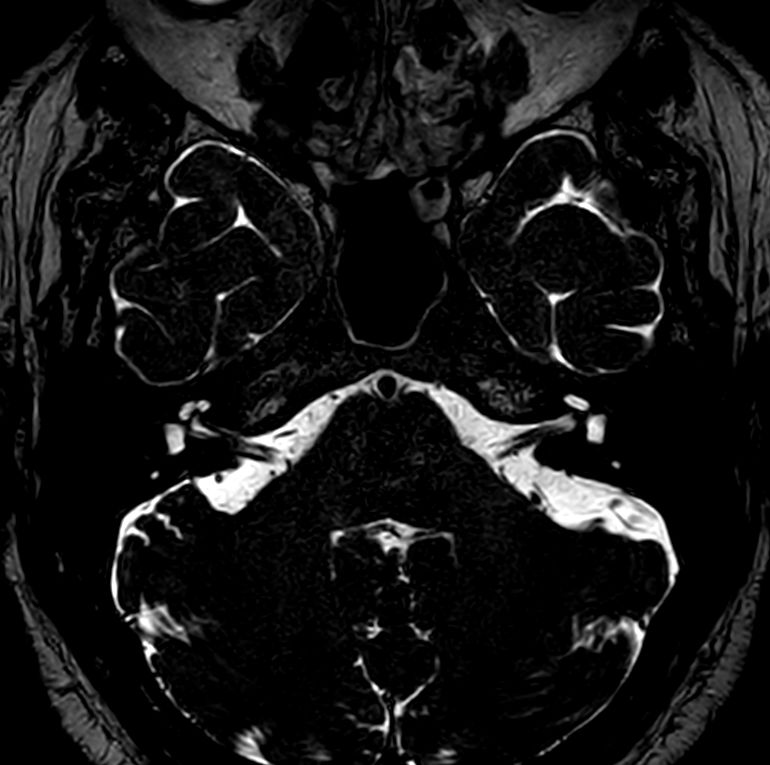

IAC - T2w TSE 3D DRIVE Compressed SENSE